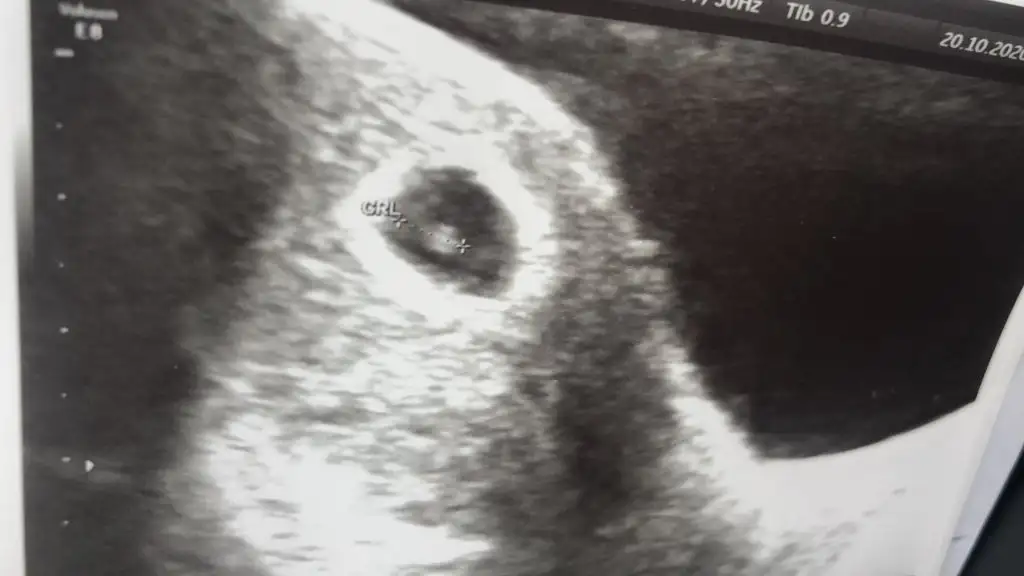

Ya ben hiç anlamam bu işlerden ama kayınvalidem şıp diye biliyor ya da sallıyor ilkinde baktı keseye erkek bu kesin dedi tuttu şimdi de baktırdık kız bunlar kesin dedi bakacağız bakalımMerhaba kızlar ben suan 6+3 gunluk hamıleyim 3 gun once tam 6 haftalıkken keseyi gorduk ve kalp atısını dinlettı doktorYa aslında bu cok onemsiz bi detay ama insan yinede merak edıyor kese şekline gore cinsiyet tahmını yapılıyormus aranızda anlayan var mı bakınca ne hissediyorsunuz

Bende anlamam böyle kese şeklinden ama bakınca erkek diye hissettimMerhaba kızlar ben suan 6+3 gunluk hamıleyim 3 gun once tam 6 haftalıkken keseyi gorduk ve kalp atısını dinlettı doktorYa aslında bu cok onemsiz bi detay ama insan yinede merak edıyor kese şekline gore cinsiyet tahmını yapılıyormus aranızda anlayan var mı bakınca ne hissediyorsunuz

Kız kesesi gibi duruyorMerhaba kızlar ben suan 6+3 gunluk hamıleyim 3 gun once tam 6 haftalıkken keseyi gorduk ve kalp atısını dinlettı doktorYa aslında bu cok onemsiz bi detay ama insan yinede merak edıyor kese şekline gore cinsiyet tahmını yapılıyormus aranızda anlayan var mı bakınca ne hissediyorsunuz

Bence kese ile cinsiyetin alakası yok benim kızımda kese fasulye gibi Di ince uzunMerhaba kızlar ben suan 6+3 gunluk hamıleyim 3 gun once tam 6 haftalıkken keseyi gorduk ve kalp atısını dinlettı doktorYa aslında bu cok onemsiz bi detay ama insan yinede merak edıyor kese şekline gore cinsiyet tahmını yapılıyormus aranızda anlayan var mı bakınca ne hissediyorsunuz